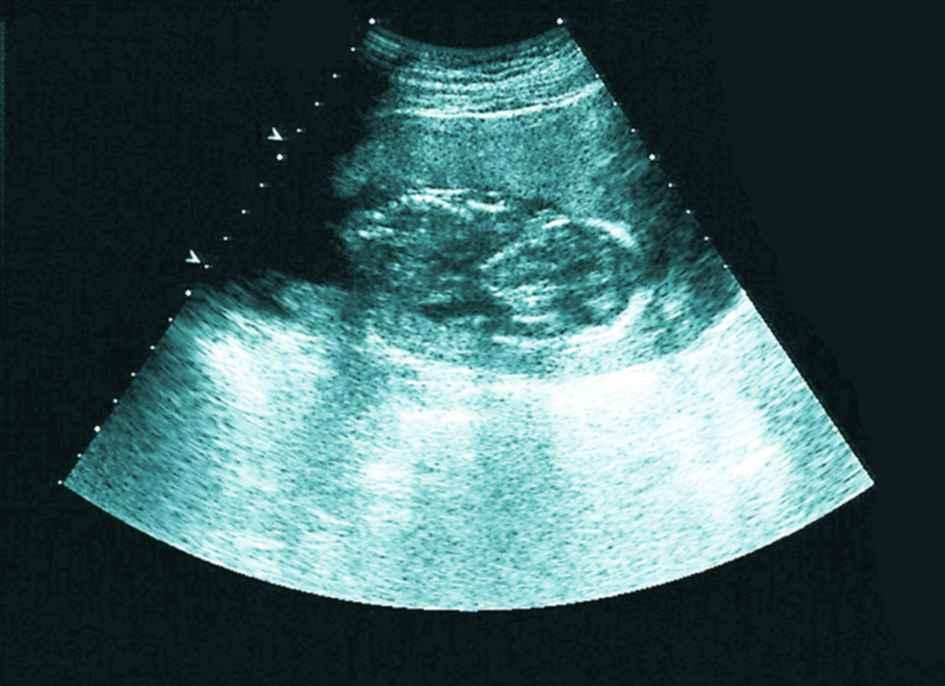

12月迟迟白带不拉丝,以为不会排卵了,到医院做了内诊和B超,又开消炎药,嘱咐我月经后通液或者造影。当时B超结果显示输卵管有优势卵泡16×14,于是回来安排功课了,没有避孕,后来几次避孕。

然而神奇的是,月经日居然测到了亲妈灰,但是颜色加深比较慢,第35天医院B超验血,没检查到孕囊,当时大夫说腹部超看不到宫外,弄得我特烦,跟他顶了几句嘴,血值hcg80不太理想,74小单位的孕酮,7天后hcg700多,又过两天hcg1044,孕酮38,也就是说在第45天,孕酮下降,于是主动B超,结果显示内膜比第35天时的薄了,且回声不均匀,宫内外都没有孕囊,大夫说孕酮下降估计是胎停,因为看不到宫内所以不给保胎。

截至能看到宫内时hcg2800多,孕酮10多一点,被宣布胎停。

孕早期,hcg数值不好,也看不到孕囊,那也不用急躁,注意看B超单,如果内膜不均匀应该是宫内孕,我在网上查阅过有姐妹这么说的,这也是我判断我不是宫外的依据。